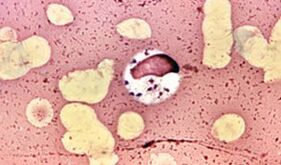

To znamená, že všechny živé organismy, které mají takové vlastnosti, patří parazitům. Ti, kteří žijí v osobě, lze rozdělit na protozoa a helminty (červy).

Nejjednodušší parazity způsobují parazitosis - onemocnění, výskyt, které vyvolávají: amobiasis, lambliosis, balalantidiáza, malárie, tripanosomóza, toxoplazmóza, trichomoniáza a další. Helminty slouží jako zdroj: Aposcaris, opisthorchiasis, echinokokóza, enterobióza a další onemocnění.

Každý typ parazitů je charakterizován vlastním vývojovým cyklem, oblíbeným stanovištěm v těle. Mohou žít ve střevech, játrech, plicích a dokonce i svalů. Někteří z nich se množí nebo se pohybují kolem průtoku krve. Pro léčbu je důležité je rozdělit na střevní a mimoškolní formy. Soukromé příznaky u parazitických chorob jsou velmi odlišné. Zvažte pouze obecné klinické příznaky přítomnosti parazitů v těle.